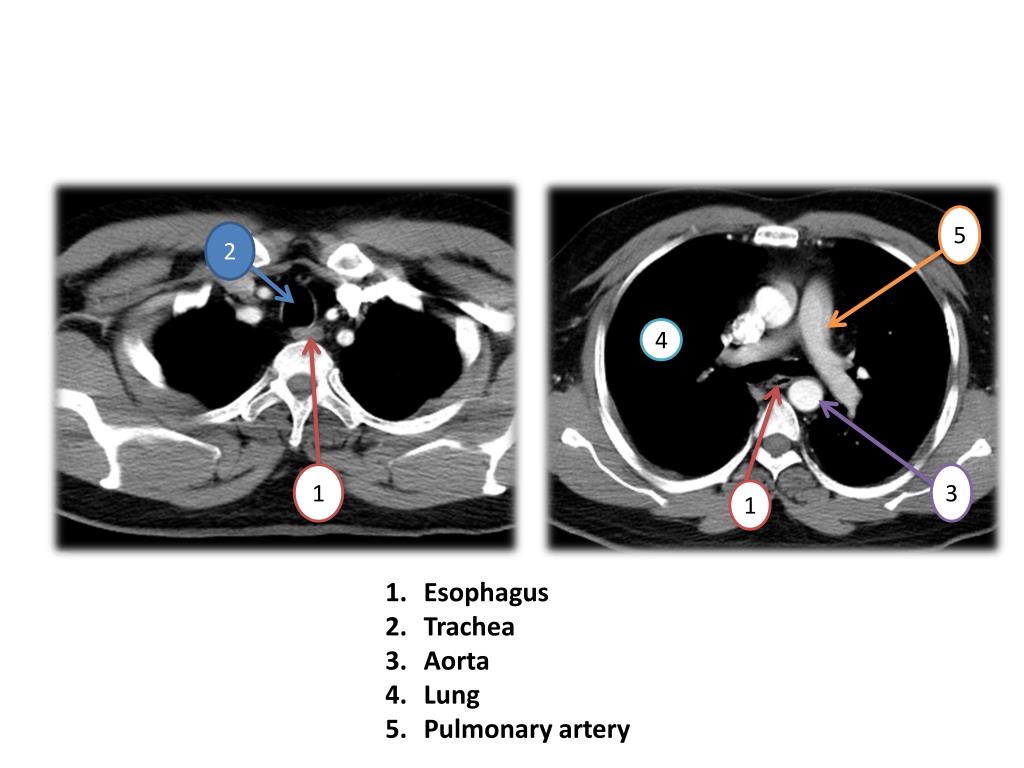

Esophageal Vestibule Radiology . Motility disorders of the esophagus are an important cause of esophageal complaints, especially when symptoms are not readily explained by a structural. From benign strictures to malignancy and motility disorders such as achalasia, imaging modalities play a significant. In esophagus part i we will discuss: Esophageal dots refer to distinct intraluminal foci on double contrast exams, which can be appear either as bright spots or focal dark lucencies or. The lower esophageal sphincter extends from the “a” to the “b” ring and is sometimes referred to as the phrenic ampulla, or vestibule. The lower esophageal sphincter, a specialized region of the circular muscle of the distal esophagus, manifests itself.

From benign strictures to malignancy and motility disorders such as achalasia, imaging modalities play a significant. In esophagus part i we will discuss: Motility disorders of the esophagus are an important cause of esophageal complaints, especially when symptoms are not readily explained by a structural. Esophageal dots refer to distinct intraluminal foci on double contrast exams, which can be appear either as bright spots or focal dark lucencies or. The lower esophageal sphincter, a specialized region of the circular muscle of the distal esophagus, manifests itself. The lower esophageal sphincter extends from the “a” to the “b” ring and is sometimes referred to as the phrenic ampulla, or vestibule.

Esophageal Vestibule Radiology The lower esophageal sphincter extends from the “a” to the “b” ring and is sometimes referred to as the phrenic ampulla, or vestibule. Esophageal dots refer to distinct intraluminal foci on double contrast exams, which can be appear either as bright spots or focal dark lucencies or. Motility disorders of the esophagus are an important cause of esophageal complaints, especially when symptoms are not readily explained by a structural. From benign strictures to malignancy and motility disorders such as achalasia, imaging modalities play a significant. In esophagus part i we will discuss: The lower esophageal sphincter extends from the “a” to the “b” ring and is sometimes referred to as the phrenic ampulla, or vestibule. The lower esophageal sphincter, a specialized region of the circular muscle of the distal esophagus, manifests itself.